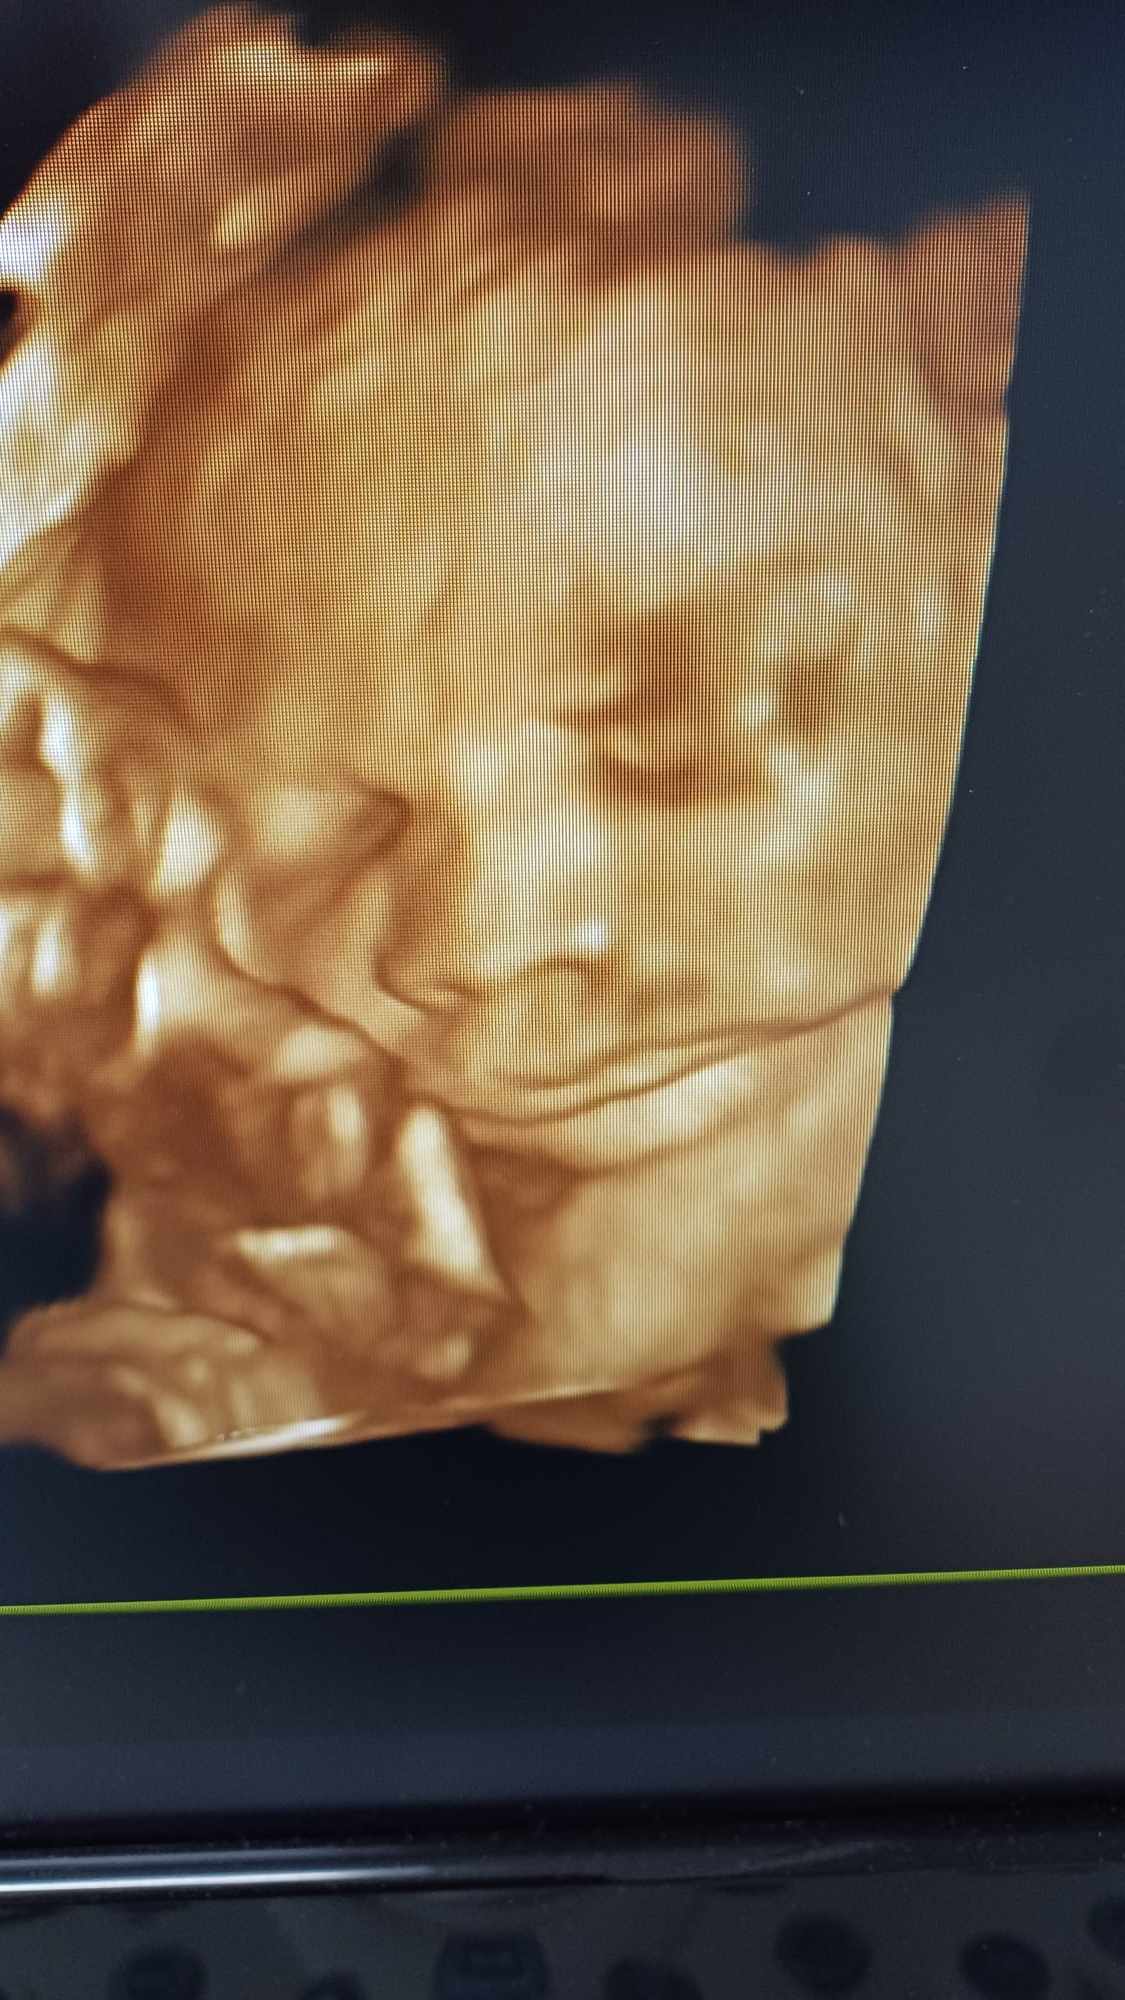

Pozrite si fotky z nášho moderného pracovného prostredia

Naša gynekologická ambulancia je vybavená modernou technikou a poskytuje pacientkom príjemné a komfortné prostredie pre všetky druhy vyšetrení a konzultácií.